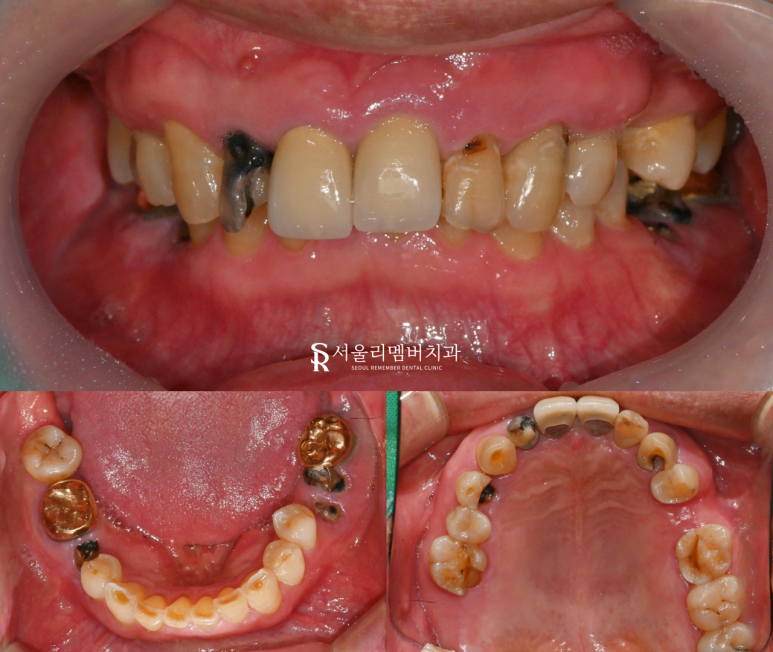

안녕하세요 낙성대 치과 박정기 원장입니다. 구내사진 06. 15 낙성대 치과 에서 구강 내 모습을 보니 생각보다 상실된 치아가 많고, 이가 빠지고 난 뒤 위생관리가 잘되지 않아 염증도 많이 생겨있습니다. 비어있는 공간이 꽤 크고 넓어서 음식을 먹는데도 불편감이 상당하고 어금니는 힘이 많이 부족해서 저작할...

낙성대 치과 에서 구강 내 모습을 보니

생각보다 상실된 치아가 많고,

이가 빠지고 난 뒤

위생관리가 잘되지 않아

염증도 많이 생겨있습니다.

비어있는 공간이 꽤 크고 넓어서

음식을 먹는데도 불편감이 상당하고

어금니는 힘이 많이 부족해서

저작할 능력도 없어 보입니다.

흔들리는 이도 많고

곳곳에 결손된 치아로 인해

치료 부위가 많아보입니다.